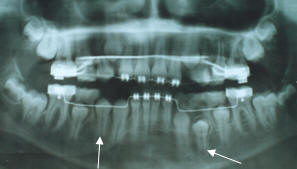

A) Panorámica.- La

dentición en términos generales aparece desarrollándose normalmente,

sin embargo hay un retraso en el proceso eruptivo de la pieza 11 y

12, se observa calcificación de los cuatro terceros molares. (Fig.

3, 4)

Fig.

3.- Radiografía panorámica del paciente de 9 años de

edad, previo al inicio del tratamiento. |